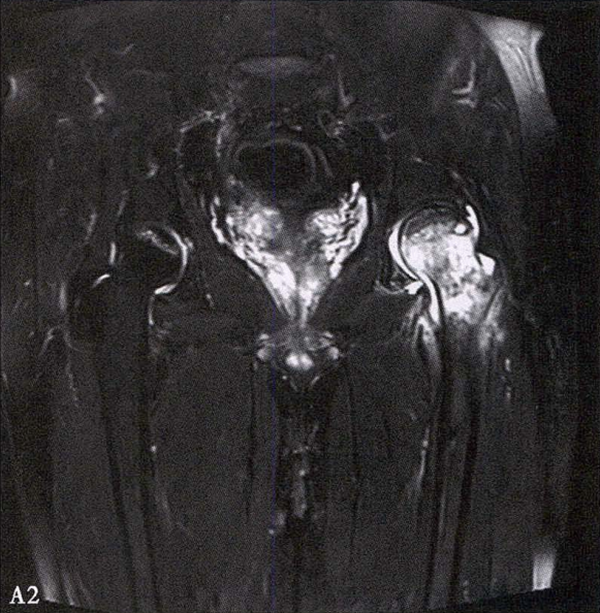

A.男性,71岁,双侧股骨头坏死,右侧Ⅰ期、左侧Ⅲ期。X线片示双侧股骨头形态可,右股骨头未见明显密度改变,左股骨头关节面下见局限性骨密度减低及增高区(A1)。MRI(T2加权像)示右股骨头内双线征,左侧不规则形混杂信号,坏死区远端骨髓水肿(A2、A3)。